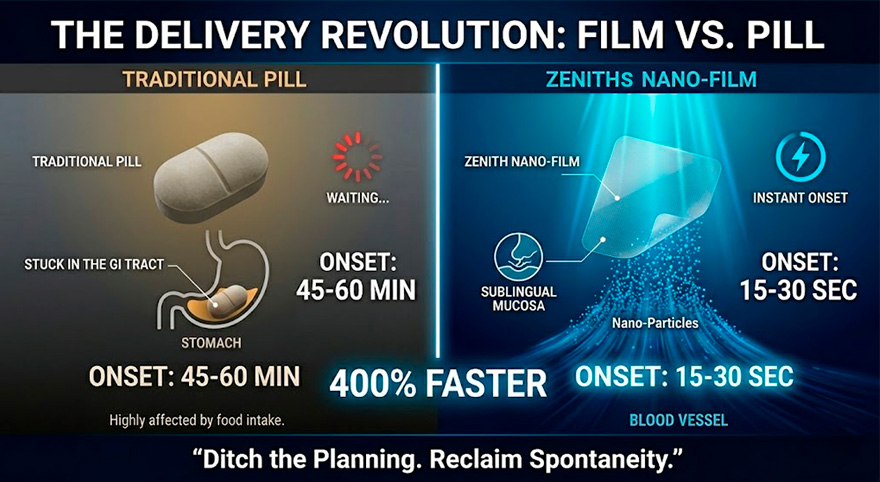

Experts highlight that ZENITHS’s effectiveness stems from its disruptive Nano-Sublingual Dissolution technology. Unlike pills or gummies that must sit in the stomach and are often hindered by food intake, ZENITHS’s active Tri-Blend formula enters the bloodstream instantly through the sublingual mucosa. By bypassing the GI tract, it accelerates onset time by over 400%. This means you no longer need to "plan" your life 60 minutes in advance; spontaneity is finally back on the table.